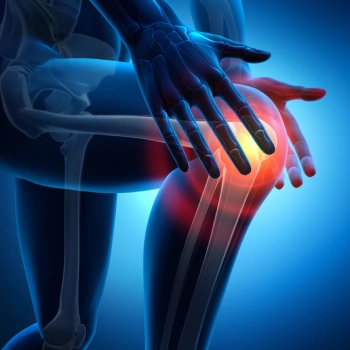

در این روش تصویر برداری یک صفحه (گیرنده یا دتکتور) در زیر عضو و قسمت مورد نظر قرار داده می شود و اشعه ایکس(دُز از اشعه جهت تشخیص) به همان قسمت که روی صفحه قرار گرفته تابنده می شود و توسط صفحه اطلاعات دریافت می شوند و همین اطلاعات پس از پردازش های لازم در نهایت عکس رادیولوژی به ما ارائه می دهد. کاربردهای رادیولوژی در منزل دقیقاً همان کاربرد رادیولوژی در بیمارستان ها می باشد از جمله بررسی انواع شکستگی ها، دررفتگی مفاصل، آرتروز مفاصل، دیدن پروتز های داخل استخوان از نظر بررسی موقعیت پروتز، آب آوردگی ریه(اِدم وافیوژن) و عفونت ریه، شکستگی دنده ها، انساد و وجود هوا در شکم و… می باشند. رادیولوژی در منزل تمام این خدمات را ارائه می دهد.

تصاویری از رادیولوژی در منزل توسط گاما پرتو